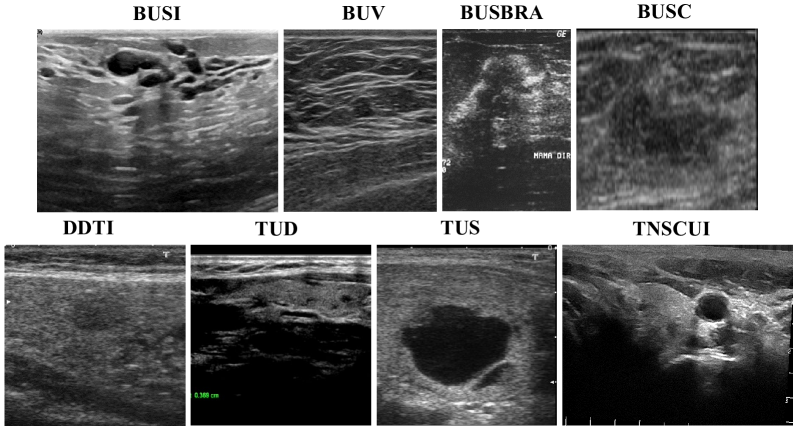

To develop a universal model for heterogeneous ultrasound (US) datasets, we built a benchmark of 4 breast and 4 thyroid US datasets. These datasets come from different sources and exhibit significant domain differences, such as variations in shadow artifacts, speckle noise, grayscale levels, and anatomical structures, as shown in Fig. 9.

Figure 9: This paper constructs an integrated benchmark comprising eight heterogeneous breast and thyroid US datasets. And the distinct characteristics of each dataset pose challenges in building a universal analysis framework.